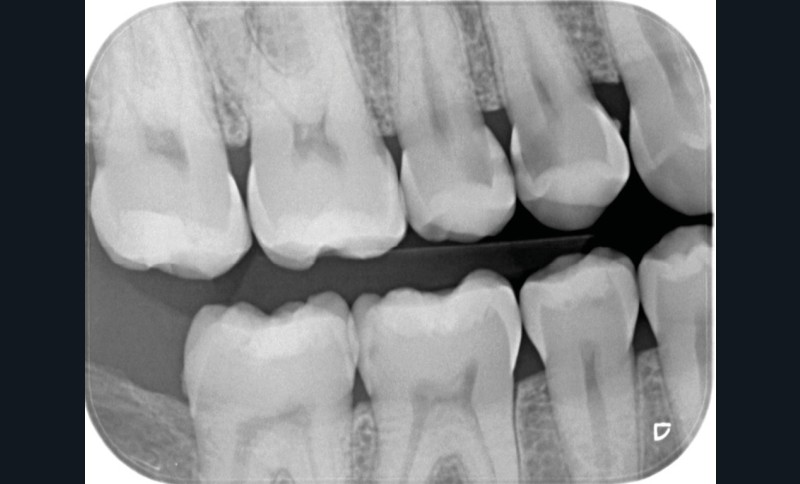

FAUX. Le diagnostic précoce des lésions carieuses se base sur un diagnostic clinique visuel précis à l’aide des classifications visuelles internationales (ICDAS ou ICCMS) et de l’utilisation d’aides optiques (loupes, microscope, caméra avec signal fluorescent ou non) et sur un diagnostic radiographique (à l’aide de deux bitewing, l’un à droite l’autre à gauche) (fig. 1).

Le choix de la prise en charge de la lésion carieuse dépend de trois critères fondamentaux : l’activité de la lésion carieuse (active ou arrêtée), la présence ou non de cavitation et l’accessibilité (site proximal difficile d’accès) (fig. 3).

• Traitement invasif a minima : il concerne les lésions carieuses cavitaires ou non avec atteinte dentinaire (à partir du 1/3 moyen dentinaire), soit ICDAS 3 à 6. Dans ce cas, la priorité est de préserver la dent d’une effraction pulpaire éventuelle (recommandations de l’ESE) [4]. C’est pourquoi, lors du traitement de lésions carieuses profondes (ICDAS 4 à 6), il faut dans tous les cas réaliser une éviction sélective, réaliser une préparation a minima (favoriser les préparations de type fente (« slot ») ou tunnel lorsque l’indication se pose) et utiliser un matériau de restauration de choix, soit composite, soit un ciment verre ionomère (CVI), soit des matériaux à base de silicate de calcium ou encore les nouveaux composites enrichis en minéraux (fig. 7 à 9). Ces préparations a minima peuvent être réalisées avec des fraises de petits diamètres (fig. 10 et 11).